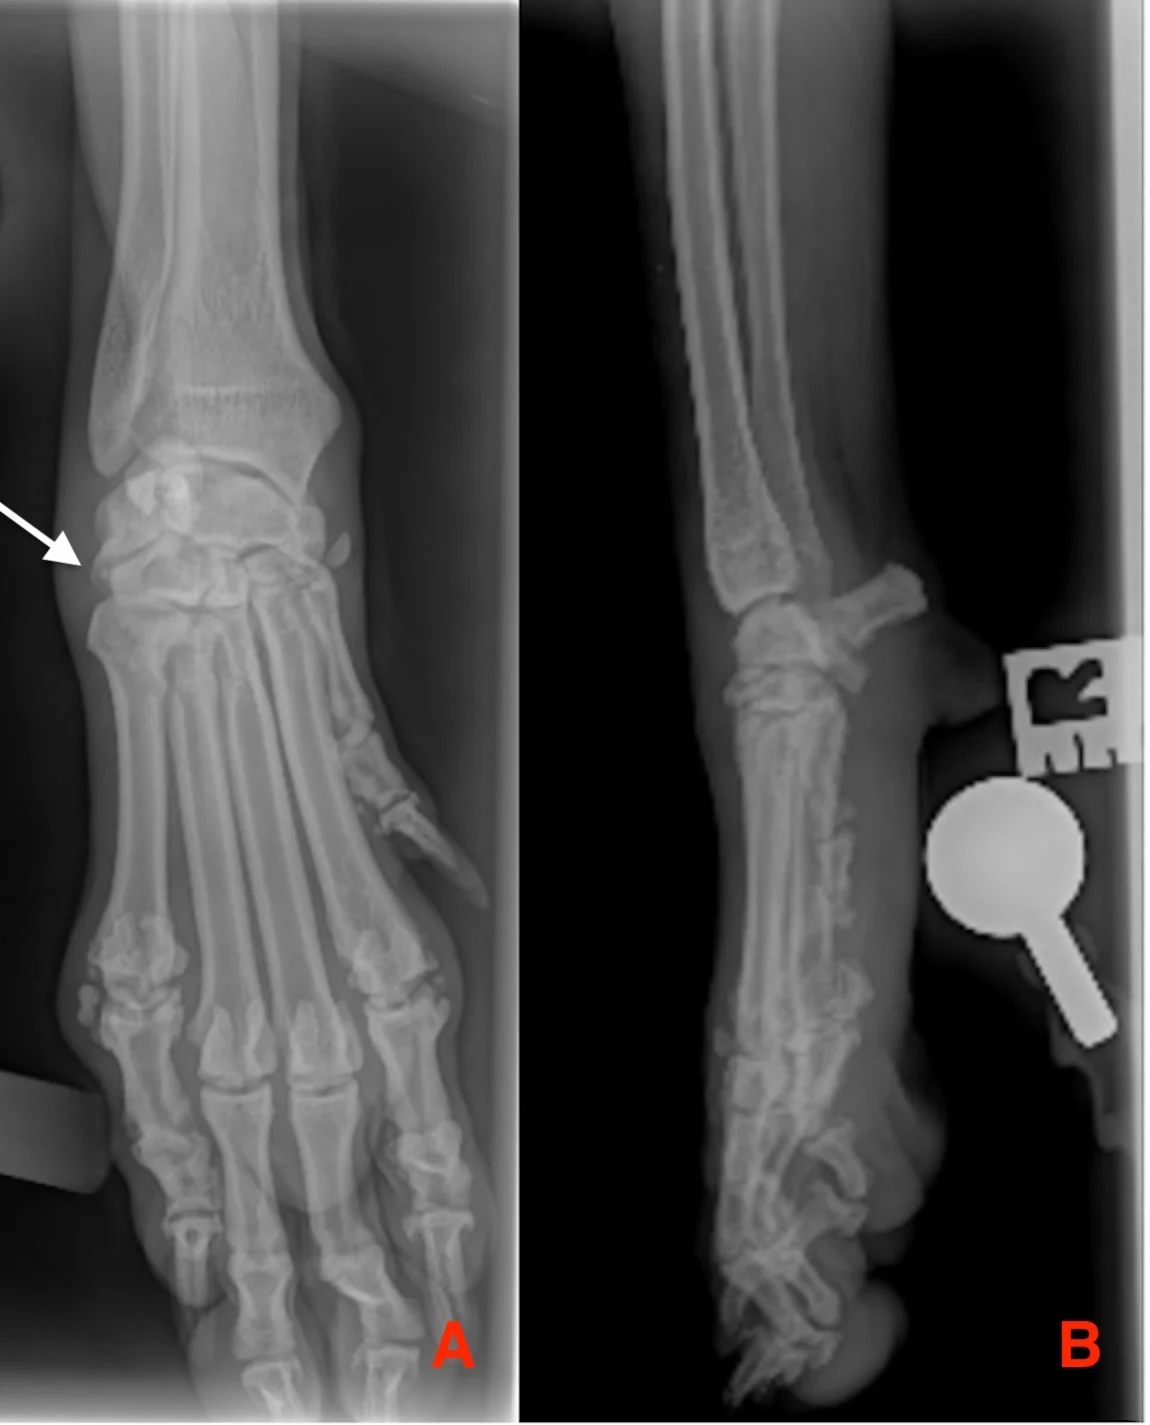

Plain orthogonal radiographs, including mediolateral oblique views (ie, dorsolateral-palmaromedial oblique, dorsomedial-palmarolateral oblique) and dorsopalmar or dorsoplantar views(Figure 4), should be obtained for lameness localized to the distal limb for confirmation of joint effusion, soft-tissue swelling, or fracture.5 Stress radiographs can then be used to determine whether there is ligament insufficiency by observing the increased space between the carpal or tarsal bones compared with the contralateral limb (Figure 5).

Dorsopalmar (A) and lateral (B) view radiographs of the carpus of a 6-year-old spayed Australian shepherd showing a right carpal injury sustained after the dog jumped a fence. Effusion is visible at the level of the carpometacarpal joint (A, arrow).